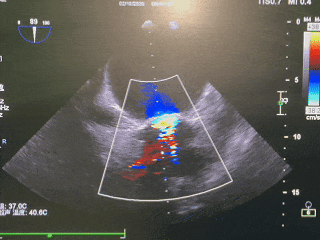

术前超声

左房内血流淤积,二尖瓣可见明显反流束

峰值血流约2.90m/s,峰值压差约34mmHg